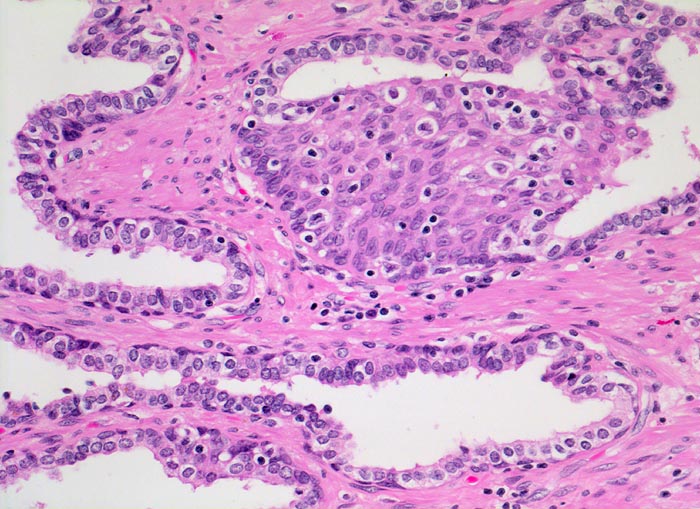

PathoPic – image database / PathoPic ID 4623 - Normale Prostatadrüsen mit Basalzellhyperplasie

Normale Prostatadrüsen mit Basalzellhyperplasie

Das normale Prostataparenchym besteht aus Paketen grösserer Drüsen eingebettet in glatte Muskulatur. Das Epithel der tubuloalveolären Drüsen ist ein- bis mehrreihig und weist eine durchgehende Schicht flachgedrückter Basalzellen auf. Nicht selten kann eine fokale Hyperplasie dieser Zellen nachgewiesen werden. Die Epithelzellen haben mittelgrosse runde bis ovale Kerne mit winzigen Nukleolen und reichlich Zytoplasma.

Die Abwesenheit der Basalzellschicht ist eines der verlässlichsten Kriterien zur Diagnose eines Adenokarzinoms. In verschiedenen benignen Läsionen ist die Basalzellschicht fragmentiert, fehlt aber praktisch nie vollständig. In Zweifelsfällen kann die Basalzellschicht immunhistochemisch nachgewiesen werden.